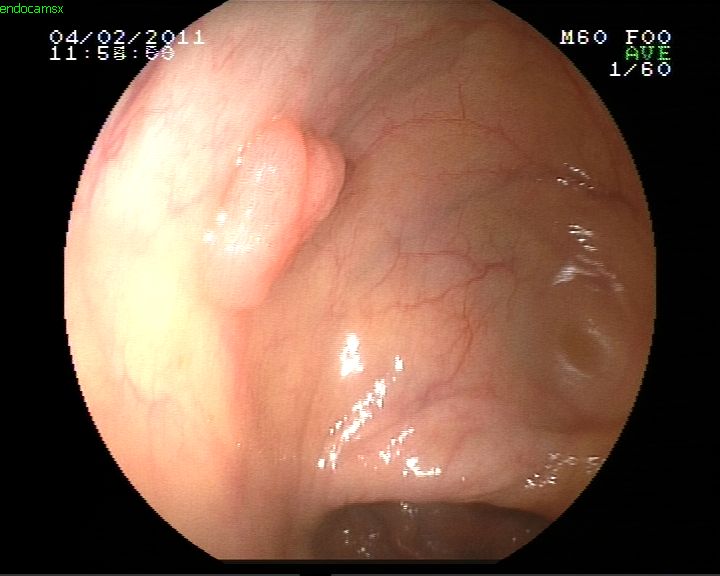

Midede polip